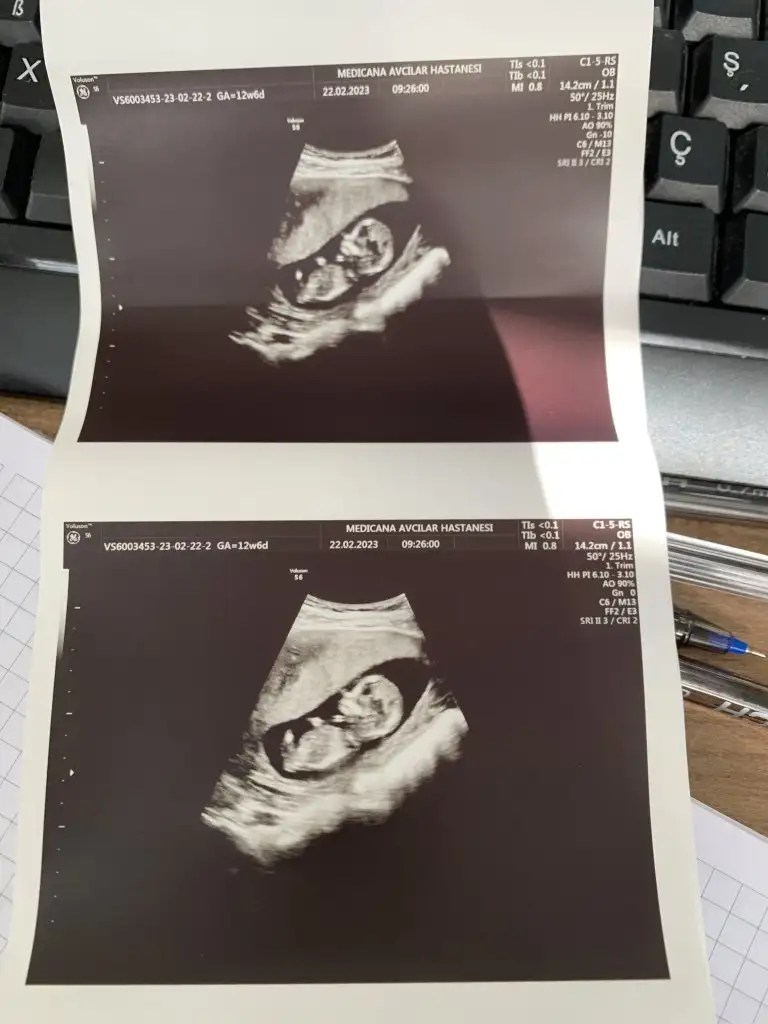

Kızlar bana da bakarmısınız

Sat a göre 12+4

Usg ye göre 13+3